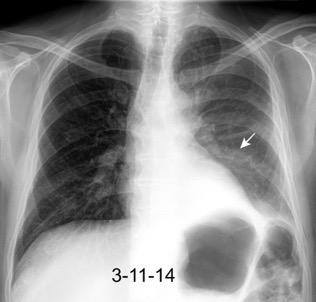

Marzo 2014: Perforación longitudinal distal secundaria a episodio de vómito (síndrome de Boerhaave). Derrame pleural izdo. que evoluciona a empiema.

Wang C-T et al. Tension hydropneumothorax in a Boerhaave syndrome patient: A case report . World J Emerg Med, 2021. Katabathina V et al. Nonvascular, nontraumatic mediastinal emergencies in adults:a comprehensive review of imaging findings. Radiographics. 2011.